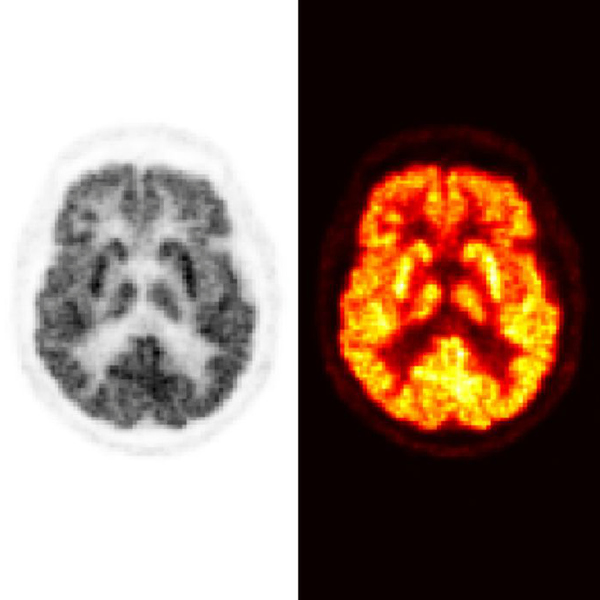

Torsdagen den 29 februari försvarar Klara Leffler, Institutionen för matematik och matematisk statistik, sin avhandling med titeln PET-samplingspusslet: Intelligenta datainsamlingsmetoder för positronemissionstomografi. Disputationen äger rum klockan 9.00 i sal BIO.E.203 – Aula Biologica, Umeå universitet.